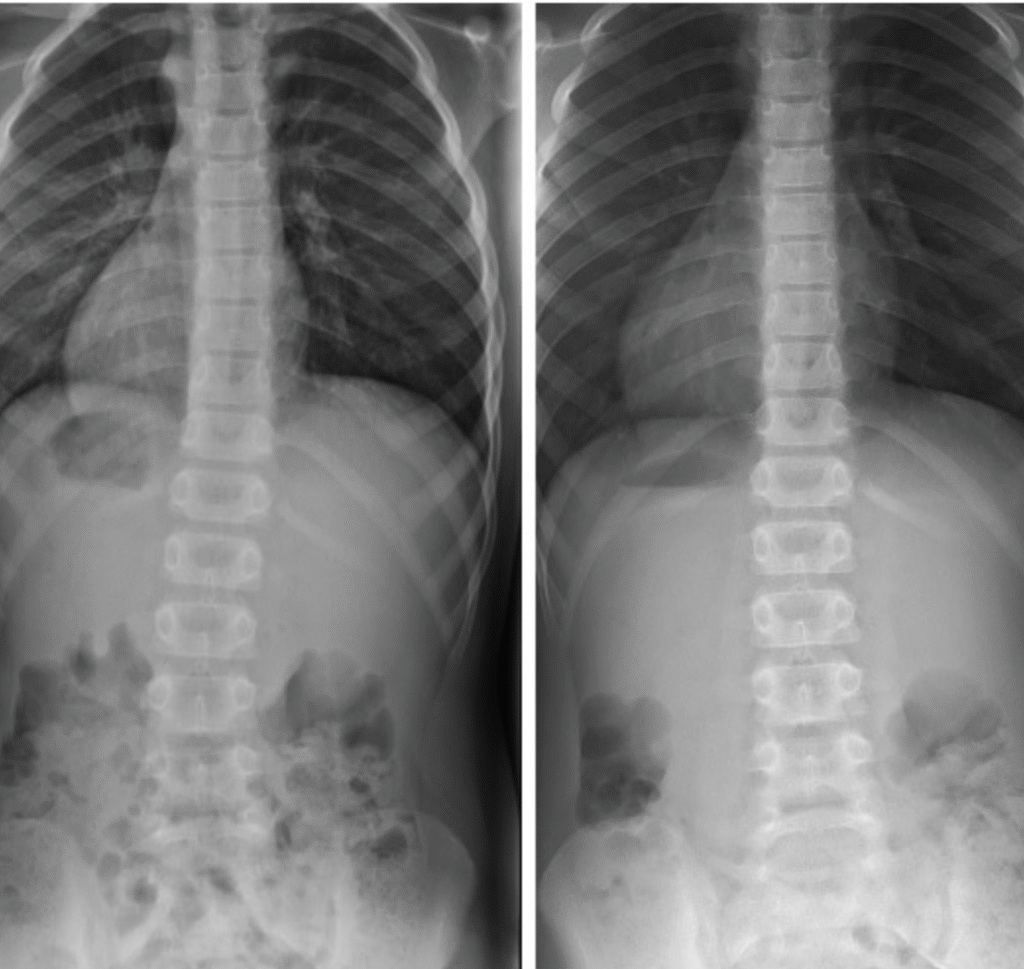

Magda – 11 lat

Terapia prowadzona w okresie 13.01 – 06.04.2016 (16 zabiegów) Częstotliwość zajęć – 10 zabiegów 2 x tydz., 6 zabiegów 1 x tydz.

Kacper – 9 lat

Terapia prowadzona w okresie 01.09 – 03.11.2016 (22 zabiegi) Częstotliwość zajęć – 2 x tydz.